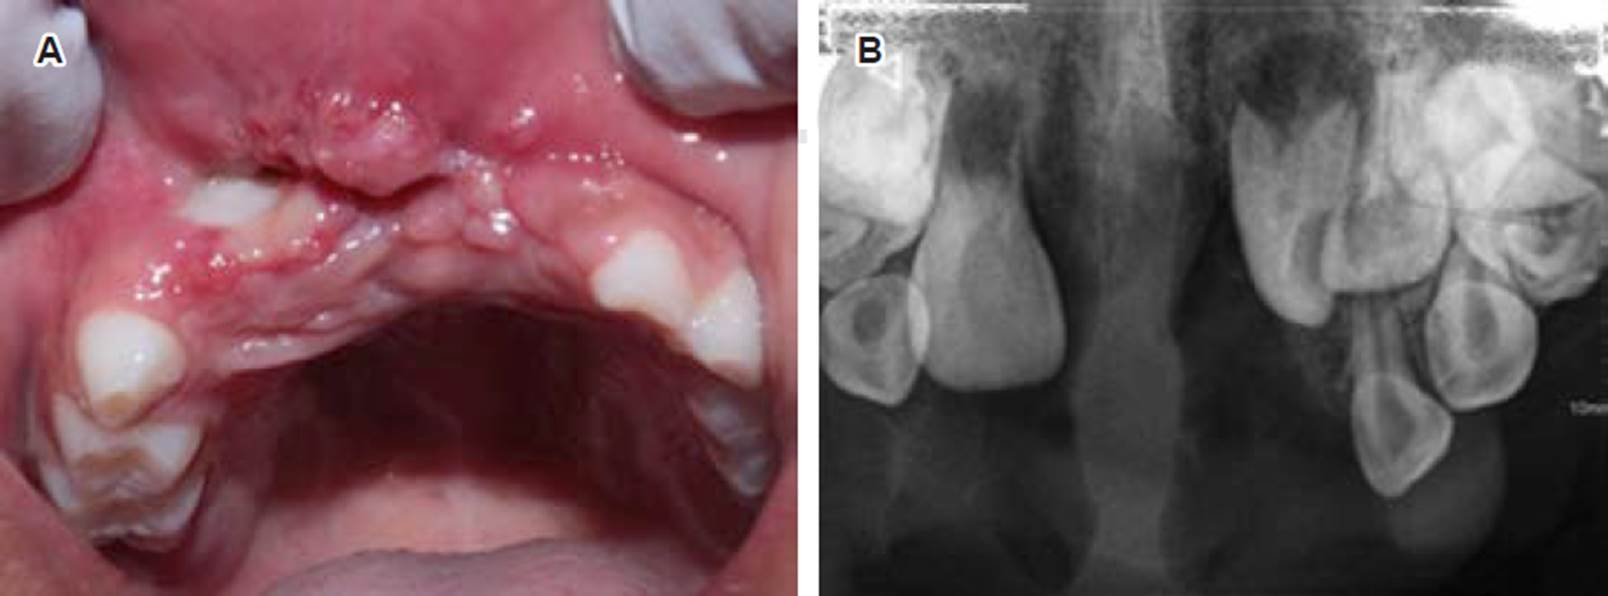

Se descartó una lesión quística y tras la evaluación multidisciplinaria se realizó exéresis quirúrgica bajo anestesia general (Figura 5). Se infiltró anestésico local (lidocaína/epinefrina), seguido de la incisión con bisturí y electrobisturí para su posterior remoción (Figura 6). Con ayuda de una legra se obtuvieron múltiples fragmentos firmes de color amarillo (de 25.0 × 25.0 x 10.0 mm la de mayor tamaño, y menor de 5.0 × 5.0 × 4.0 mm) y se suturó. Se determinó histopatológicamente la presencia de células gigantes multinucleadas (Figura 7), lo que permitió confirmar que se trató de un granuloma central de células gigantes. Se retiraron los puntos 10 días después de la intervención.

Se examinó tres semanas después en la Clínica de Odontopediatría de la Universidad Autónoma de Zacatecas para evaluar la evolución clínica y radiográfica (Figura 8), donde se apreció la cicatrización de los tejidos blandos involucrados. Se observó además la exposición de un incisivo central en el vestíbulo de la lesión, y radiográficamente se apreció la presencia de los dientes 11,21 y 22 aún con formación radicular incompleta.